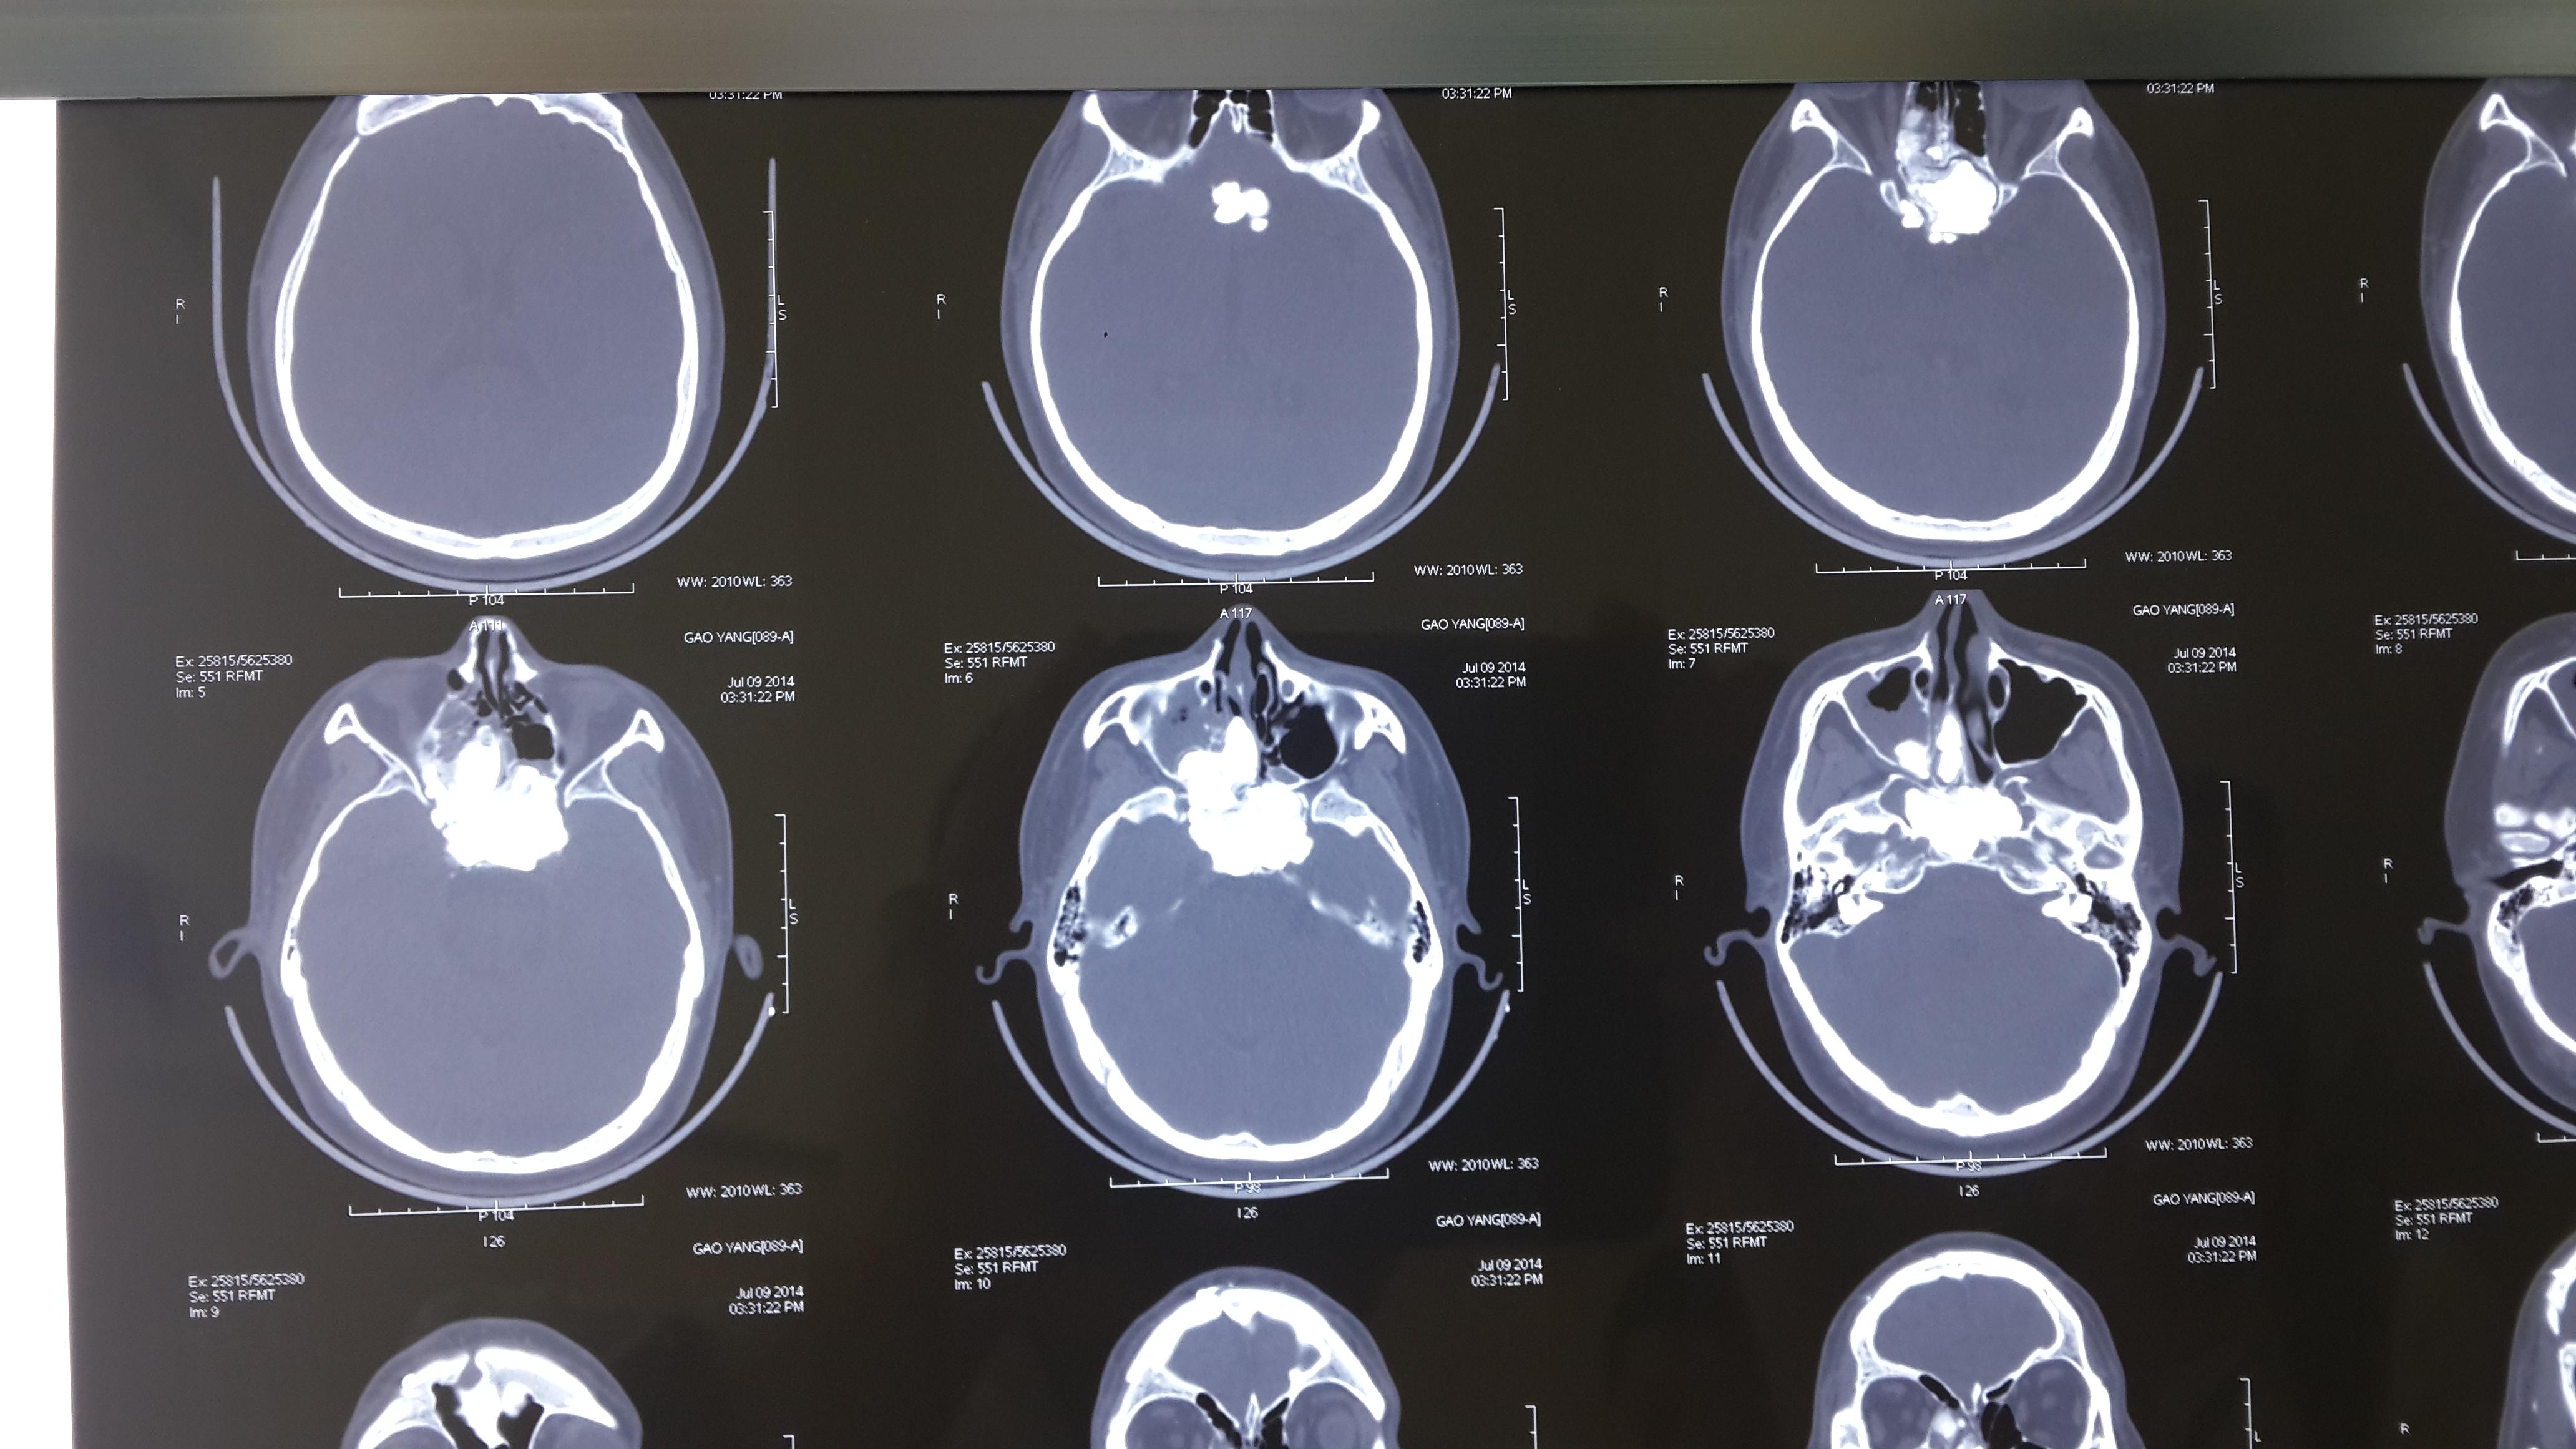

一例重型颅脑损伤一期颅骨成形术和颅底修补术的诊疗体会

入院头颅ct:前颅底等密度病灶,右侧额叶低密度软化灶

急诊头颅ct扫描显示左侧硬膜下血肿,可疑性颅底骨折不除外